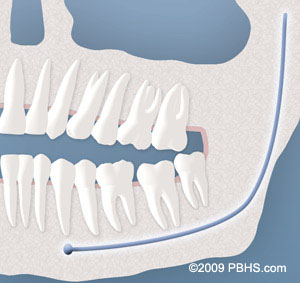

Soft Tissue Impaction

There is not enough room to allow the gum tissue to retract for adequate cleaning of the tooth.

Partial Bony Impacted Wisdom Teeth

There is enough space to allow the wisdom tooth to partially erupt. However, the tooth cannot function properly in the chewing process, and creates cleaning problems, among others.

Complete Bony Impaction

There is NO space for the tooth to erupt. It remains embedded in the jaw bone or if even partially visible requires complex surgical techniques for removal. The impacted wisdom tooth may also be in an unusual position and difficult to remove. This situation can also arise when the shape or size of the jaw bone and other facial structures make removal of this tooth significantly more complex.